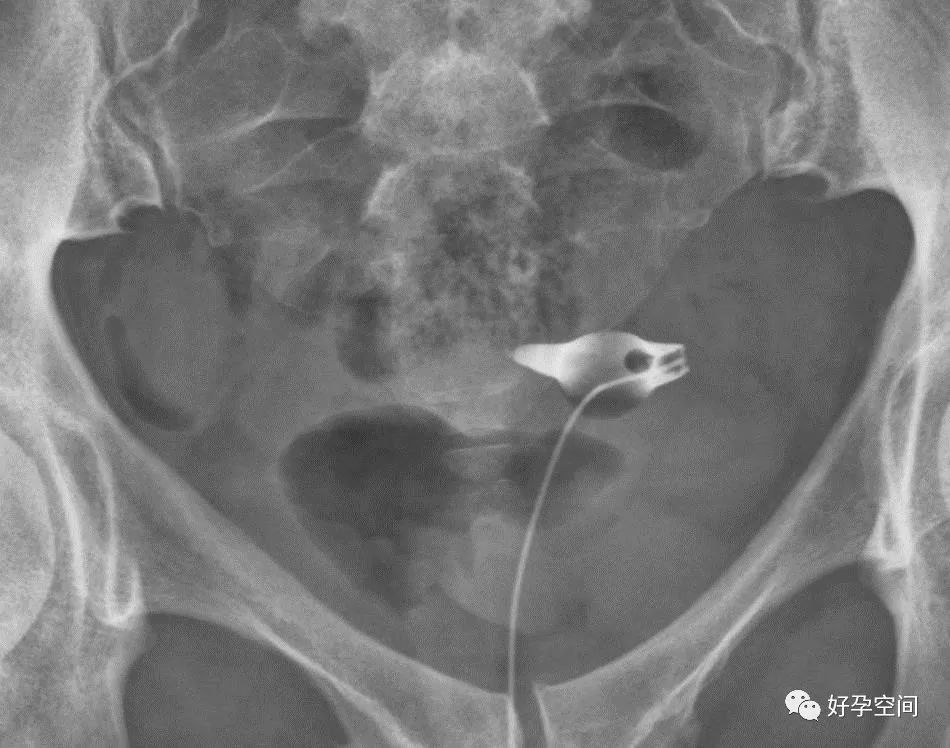

6、子宫肌瘤钙化

盆腔内见类圆形蛋壳样高密度影

7、畸胎瘤钙化

盆腔内见牙齿状高密度钙化影